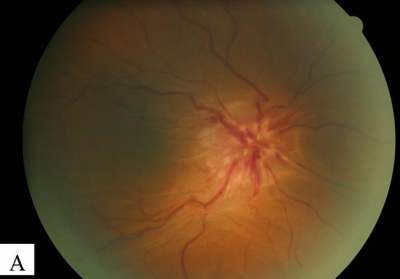

Funduscopy of the right eye showed that the optic disc was swollen and hyperemic. Disc hemorrhages were present at 2, 4, 6 and 10 o’clock position. Retinal veins were dilated and tortuous. Retinal arteries were tortuous but not dilated. Spontaneous venous pulsation was absent. There were prominent choroidal folds which were seen more obviously with the red free light. The macula was involved with the loss of foveal reflex (Figure 3). A flamed shaped hemorrhage was seen below the superior temporal arcade. There were no cotton wool spots, retinal edema, hard exudates, retinal or choroidal detachment and no choroidal mass.

Figure 3